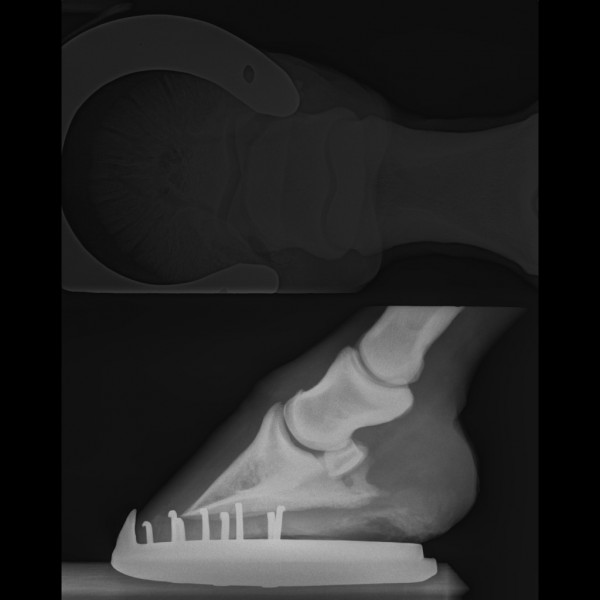

Voici les clichés de mon cheval avec une sole très fine, on voit bien que la pointe de la troisième phalange est très proche du sol, surtout sur l'antérieur droit :

Il n'était pas encore ferré sur ces radios. Je l'ai fait depuis ce temps car il marchait très mal.

sur les radios, on voit que le cheval n'est pas ferré (ce qui est beaucoup mieux pour les radios) et qu'il a effectivement les soles fines. à droite, pas de problème d'hyperostéose. à gauche, il y en a un peu mais ça reste discret. par contre, même si la radio est décalée, il y a une suspicion d'arthropathie sur l'articulation 2-3 phalangienne...